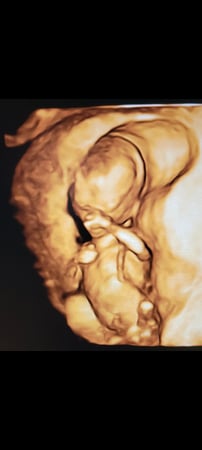

Tasha Crump, is registered by the American Registry of Diagnostic Medical Sonographers (ARDMS) and have over 18 years experience in medical diagnostic sonography specializing in Maternal Fetal Medicine. She is a highly proficient in the art of 3D 4D ultrasound. Tasha has practiced and trained in NYC's top ranked hospitals including Columbia Presbyterian. At Love at First Sight Imaging Studio you'll be in a very comfortable and calming atmosphere for you and your family to bond with your baby. We have state of the art equipment with HD Live to image unbelievably realistic views of your baby. You will fall in Love at First Sight.